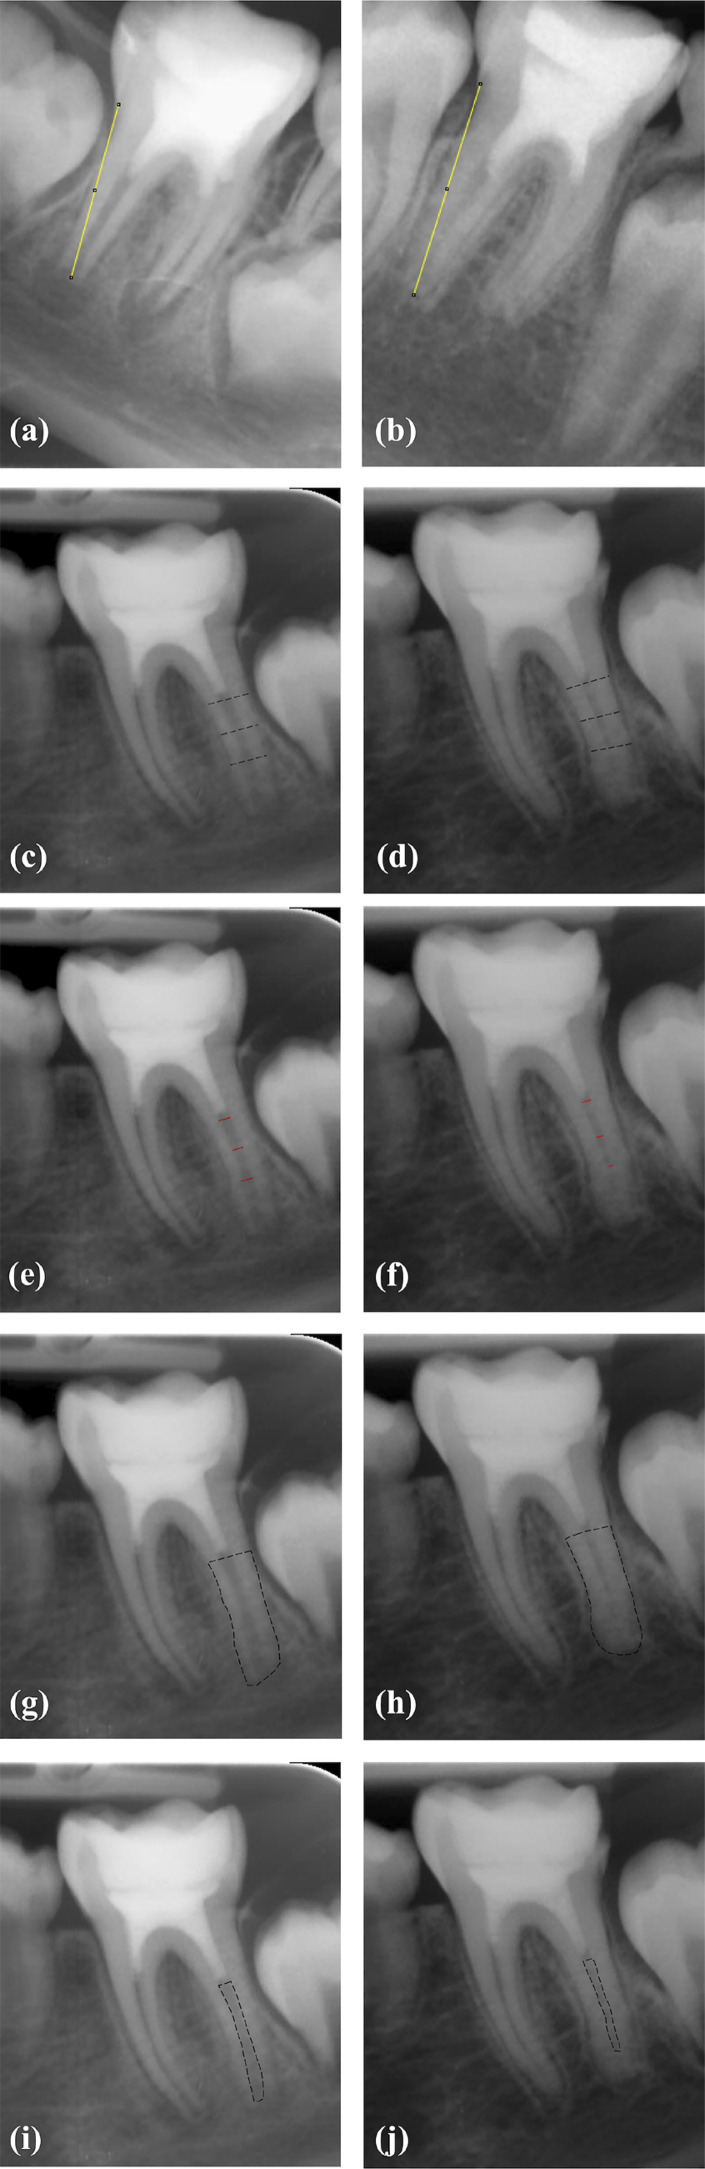

Objective: The primary goal is to evaluate the effects of two different intracanal medicaments, calcium hydroxide [Ca(OH)2] and double antibiotic paste (DAP), on radiographic outcomes during regenerative endodontic procedures (REP) of immature permanent mandibular first molars with symptomatic irreversible pulpitis and symptomatic apical periodontitis (SIP/SAP). Additionally, the secondary goal was to evaluate MMP-8 levels during REP using two different intracanal medicaments.

Methodology: The study included 20 patients with immature mandibular first molars exhibiting SIP/SAP. Participants were randomly assigned into two groups based on the applied intracanal medicament. Ca(OH)2 (n=10) was prepared by mixing it with sterile distilled water, while the same amount of powdered metronidazole and ciprofloxacin were mixed and combined with sterile distilled water for DAP (n=10). MMP-8 in periapical samples were measured at baseline and on the 14th day using immunofluorometric assay. Image-J software with TurboReg plug-in was utilized to determine changes in root length, root width, radiographic root area (RRA) during the 12-month follow-up period. Data were analyzed by SPSS 25.0 (p<.05).

Results: Significant increase in MMP-8 on the 14th day compared to baseline in both groups (p<0.001). There was no significant difference between the two groups in terms of the increase in MMP-8 (p>0.05). Root length significantly increased in both groups (p=0.001), with Ca(OH)2 showing a greater increase (p=0.046). Root width and RRA increased similarly in both groups at 12th month.

Conclusion: Both Ca(OH)2 and DAP applications resulted in a significant increase in periapical MMP-8 levels. Increase in radiographic root width and root area was similar between two groups, but Ca(OH)2 led to a significantly greater increase in root length. Further studies with larger sample sizes are necessary to validate our findings during REP of vital immature permanent mandibular molars. Clinical Trials database: NCT05581706.